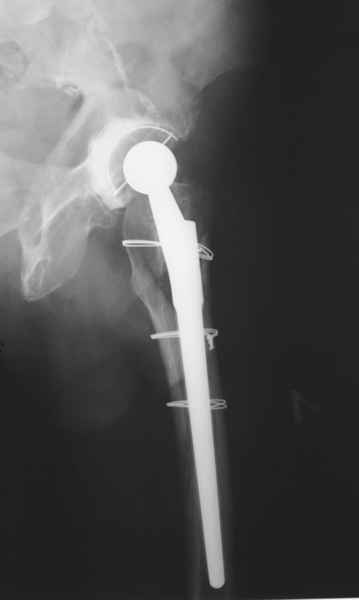

Произведено закрытое удлинение ножки эндопротеза с помощью ретроградного интрамедуллярного стержня. Продолжительность операции 3 часа. Два из них закрытое восстановление длины бедра диистрактором

таз-бедро.

новые снимки

Пациента удалось осмотреть недавно. Достигнутый результат сохраняется. Перелом бедра сросся. Конечность опорная и безболезненная, ходит без трости. Ножка, похоже, реинтегрировалась, как и надеялись. Снимки и фото в приложении. Комментарии приветствуются.

Надо ли что-то делать дальше, как полагаете? Убрать винты? Убрать "удлинитель ножки"? Или оставить все, как есть? Спасибо заранее.